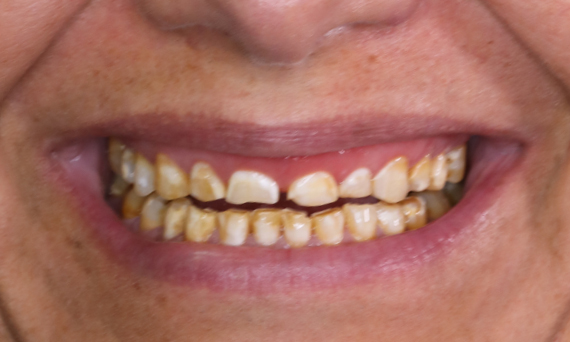

Rehabilitación del cuadrante en 2 sesiones

Diez coronas individuales VITA Suprinity PC

El paciente quería una sonrisa hermosa. Dado que los dientes 15 a 25 son visibles, se tomó la decisión de usar una cerámica altamente estética para los 10 dientes. Debido a la amplia consulta y a la implementación con un modelo a escala, la restauración se llevó a cabo en dos sesiones con CEREC.

Antes: La paciente quedó insatisfecha con su sonrisa debido a la decoloración de los dientes.

Después: Diez coronas individuales altamente estéticas, individualizadas con manchas.